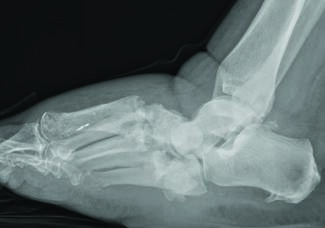

Surgeons typically recommend a period of non-weight-bearing after open reduction and internal fixation (ORIF) of ankle fractures, but what does the evidence actually tell us about for how long and under what circumstances this is effective?...

Surgeons typically recommend a...